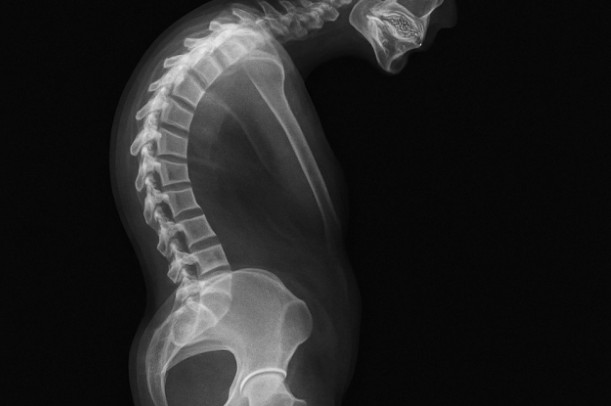

骨盤の後ろが痛いと感じる場合、多くは腰の少し下、お尻の上部から中央あたりにかけて違和感や重さが出やすい状態を指すと言われています。この部分は骨盤と背骨、股関節が近くに集まっており、体を支える土台として常に負荷がかかりやすい場所でもあります。そのため、動いたときだけでなく、座っている最中や立ち上がる瞬間に痛みを意識するケースも少なくないようです。

骨盤は腰や股関節、背骨と連動して動くため、どこか一部の動きが硬くなると全体のバランスが崩れやすいと言われています。例えば、股関節の動きが小さくなると、その分を骨盤や腰で補おうとするため、後ろ側に負担が集中しやすくなることもあるようです。体全体の動きのつながりを意識することが、原因を考えるうえでの手がかりになると考えられています。